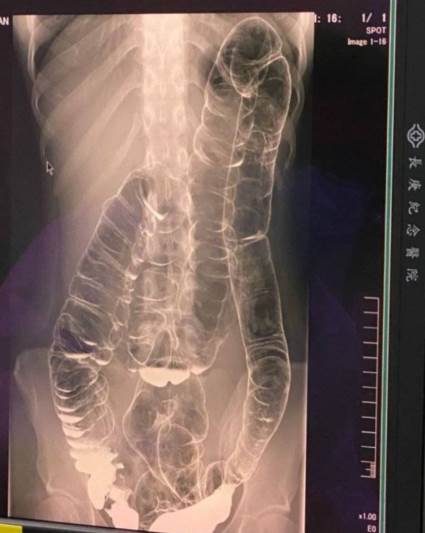

根據媒體《Sanook》的報導,2020年,台灣有一名23歲女子因長達17天沒有排便,嚴重便祕,導致糞便直接衝破結腸,堆積並擠壓至胸腔,她差點因此喪命。雖然女子後來經過手術撿回一命,卻也因此失去部分腸道功能,需終身調養。